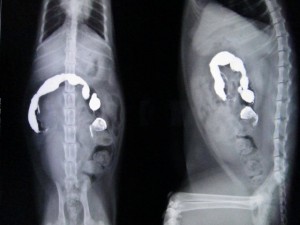

バリウム術前2

次の日のレントゲンです。

バリウムは結腸まで通貨していますが、胃内に不透過物が残っています。